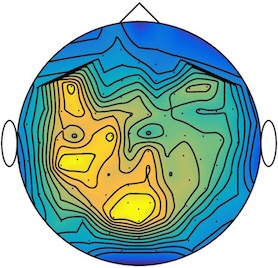

We applied our method to a magnetoencephalography (MEG) dataset. In this setup, brain activity of a subject is recorded (Elekta Neuromag, 306 sensors of which 204 planar gradiometers and 102 magnetometers, sampling frequency 1000Hz) while the subject reacted to the presentation of a target stimulus by pressing either the left or the right button.

Data is preprocessed applying signal space separation correction, interpolation of noisy sensors, and realignment of data into a subject-specific head position (MaxFilter, Elekta Neuromag). The signal was then filtered (low pass 40HZ), and artifacts such as blinks and heartbeats removed thanks to Signal-Space Projection using the Brainstorm software222http://neuroimage.usc.edu/brainstorm. The samples we used for our barycenter computations are an average of the norm of the two gradiometers for each channel from stimulation onto 50ms and the classes were left or right button.

| Class 1 | Class 2 | ||||||

|

|

|

|

|

|

|

|

| Sample 1 | Sample 2 | Sample 3 | Mean | Sample 1 | Sample 2 | Sample 3 | Mean |

|

|

|

|

|

|

|

|

This results in two classes of recordings, one for each pressed button. We aim at computing a representative activity map for each class using Wasserstein barycenters. For each class we have recordings each having samples located on the vertices of an hexahedral mesh of a hemisphere (corresponding to a MEG recording helmet). These recorded values are positive by construction, and we rescale them linearly to impose . Figure 6, top row, shows some samples from this dataset, displayed using interpolated colors as well as iso-level curves. The black dots represent the position of the electrodes on the half-sphere of the helmet, flattened on a 2-D disk.

We computed TV-regularized barycenters independently for each class by solving (16) with the TV regularization using the projected gradient descent method (22). We used a squared Euclidean metric (24) on the flattened hemisphere. Since the data is defined on an irregular graph, instead of (23), we use a graph-based discrete gradient. We denote the graph which connects neighboring electrodes. The gradient operator on the graph is

The total variation on this graph is then obtained by using , the norm, i.e. we use in (23).

Figure 6 compares the naive barycenters (i.e. the usual mean), barycenters obtained without regularization (i.e. ) and barycenters computed with an increasing regularization strength . The input histograms being very noisy, the use of regularization is important to make the area of significant activity emerge from the noise. The use of a TV regularization helps to keep a sharp transition between active and non-active regions.